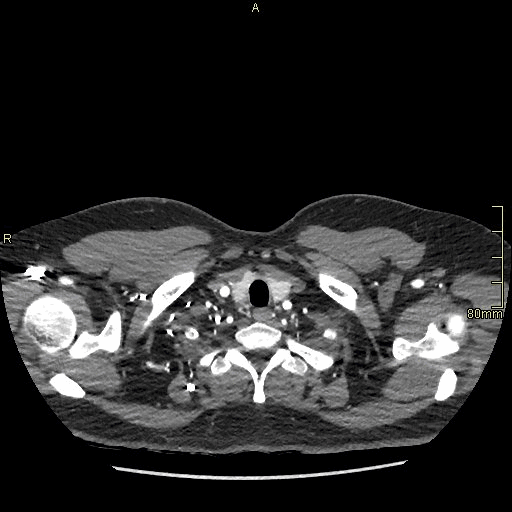

Chest/Abdomen Angiogram (Axial)